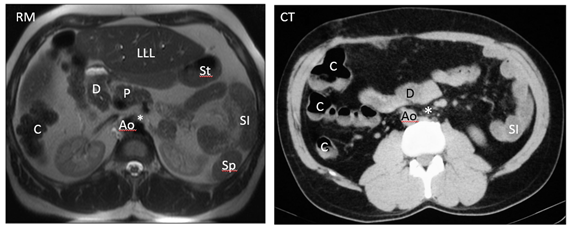

Figure 4 Axial MR and CT images show a prominent left hepatic lobe (LLL), colon on the right (C), small intestine on the left (SI), truncated pancreas (P), left-sided stomach (St), one splenule on the left (Sp), Aorta on the right (Ao) and intestinal malrotation because the duodenum (D) does not pass between the aorta and the superior mesenteric artery (asterisk). IVC cannot be identified.